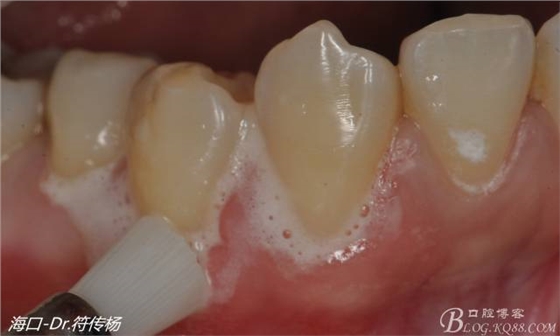

術(shù)前處理:

我們首先需要使用拋光刷+拋光膏清潔根面

然后使用EDTA處理根面2min利于牙周附著(有爭(zhēng)議)